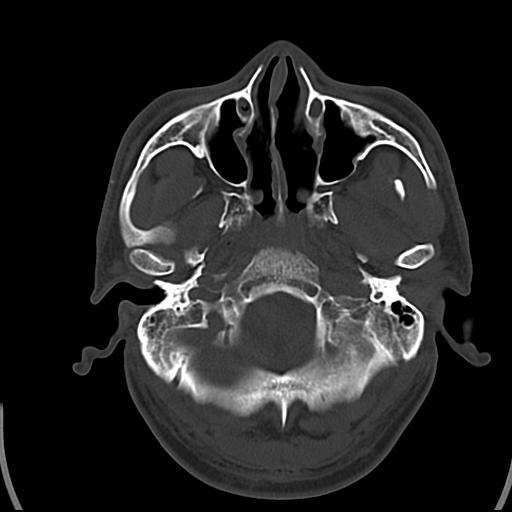

头皮下高密度结节影???临床上在老年男性比较常见。大家看看是什么?成因是? 本例患者,男性,51岁。外伤来诊。无染发史及发根植入史。

这种东西有时要结合触诊和望诊。